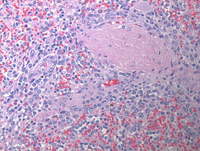

HE images of splenectomy

At low power, multiple discrete white pulp nodules are noted. On higher power these nodules are monotonous with replacement of the white pulp by small to medium sized lymphoid cells with occasional plasmacytoid cells.